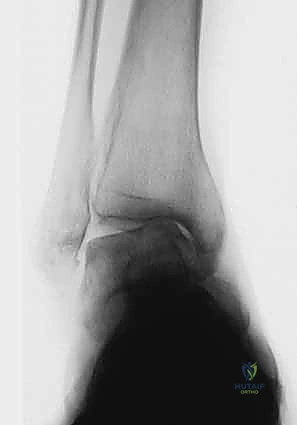

| المرحلة الأولى (المبكرة) | لا يوجد تضيق ملحوظ في المسافة المفصلية. ظهور تصلب عظمي مبكر (Sclerosis) وتكون نتوءات عظمية صغيرة (Osteophytes) في الزاوية الأمامية الإنسية. | الغضروف لا يزال سليماً بنسبة كبيرة، المسافة المفصلية طبيعية. | ألم خفيف بعد المجهود الطويل، تيبس بسيط في الصباح. |

| المرحلة الثانية (المتوسطة) | تضيق واضح وغير متماثل في المسافة المفصلية، يتركز بشكل أساسي في الجانب الإنسي (الداخلي) للكاحل. | ترقق ملحوظ في الغضروف الداخلي، بداية احتكاك غير مباشر. | ألم متكرر مع المشي، تورم متقطع، بداية ملاحظة ميلان القدم. |

| المرحلة الثالثة (المتقدمة) | طمس شبه كامل للمسافة المفصلية مع تلامس العظم تحت الغضروف في الجانب الإنسي. تنقسم إلى: 3أ: الطمس يقتصر على وجه الكعب الإنسي. 3ب: الطمس يمتد لسقف قبة الكاحل. |

تآكل شديد للغضروف، احتكاك مباشر للعظم بالعظم في الجانب الداخلي. | ألم شديد يعيق الأنشطة اليومية، تورم مزمن، عرج واضح أثناء المشي. |

| المرحلة الرابعة (الشديدة جداً) | طمس كامل للمسافة المفصلية بأكملها (الإنسية والوحشية). تلامس واسع للعظم بالعظم، تشوه شديد في بنية المفصل. | غياب تام للغضروف المفصلي الفعال. | ألم مستمر حتى أثناء الراحة، فقدان كبير في مدى الحركة، تشوه واضح للعين المجردة. |

2. التصوير بالأشعة السينية بوضعية الوقوف (Weight-bearing X-rays)

هذا هو حجر الأساس في التشخيص. الأشعة العادية والمريض مستلقٍ لا تظهر الحجم الحقيقي للتشوه. يطلب الدكتور هطيف صوراً خاصة والمريض يحمل وزنه كاملاً على قدميه.

* المنظر الأمامي الخلفي (AP View): لتقييم المسافة المفصلية وتحديد زاوية سطح الساق (Tibial Anterior Surface Angle - TAS).